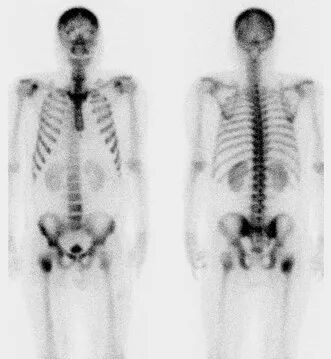

核医学检查SPECT

辐射:有,不大,0.1-5.2mSv

大家不要谈“核”色变!SPECT全称“单光子发射计算机断层成像术”,它是针对人体内组织血流、功能代谢及生理生化成像。

它的检查原理是借助于微量核素药物、现代医学影像技术与分子生物学相结合的新技术,高灵敏反映人体内组织器官的血流灌注、功能代谢及生理生化的成像方法。

SPECT 检查的用途非常广泛,主要用于早期推断脑、心脏、肾脏、肝、肺、甲状旁腺等人体各脏器的功能改变,血液供给和代谢改变等。如:

1.全身骨显像(4.2mSv):一次检查可以对全身骨骼进行扫描,对各种良恶性骨疾病的灵敏度非常高(可探测出90%以上的病变)。

SPECT检查辐射量不高 ,不会对周围医护人员、家属造成辐射损伤。

全身骨显像可较X等影像检查提前3-6个月发现骨转移灶。上图中X片显示阴性(右),但骨显像(左)发现右侧股骨上端骨转移灶。